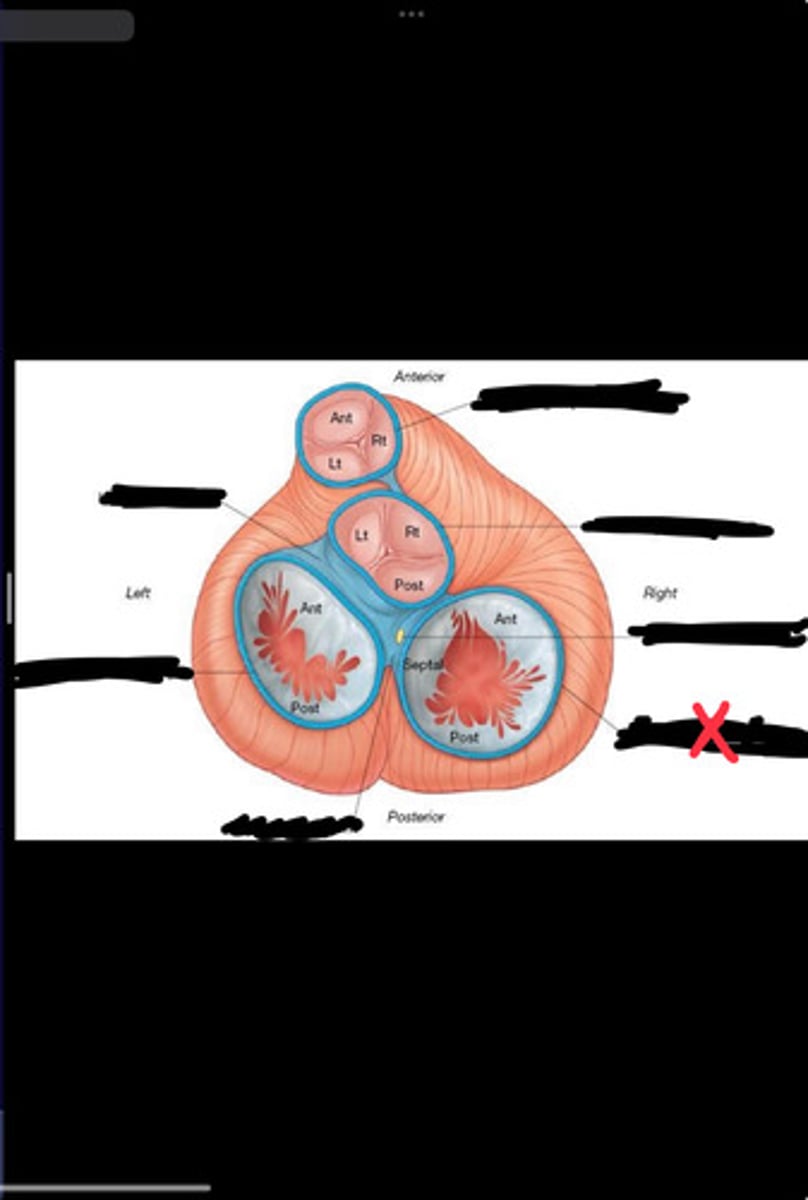

Right fibrous trigone

Left fibrous trigone

Fibrous ring of pulmonary valve

Fibrous ring of aortic valve

Atrioventricular bundle

Right atrioventricular ring

Left atrioventricular ring